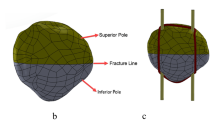

a The coordinate system of the patella. K-wires were placed in the direction of the y-axis (SP 3 for example). b Projection of all SPs on the median transverse section of the patella. SP 1–5 (red dots) were included in this study, and the most anterior and most posterior SPs (black dots) were excluded

Two K-wires were placed in a parallel fashion along the direction of the y-axis and on the quarter lines of the median transverse section (Fig. 1a). Note that we focused only on the SP of K-wires (the direction of the z-axis) but not the coronal position (the direction of the x-axis). Thus, among all models, K-wires kept coinciding with the medial and lateral quarter lines, respectively on the AP view. SPs were determined by the following method. Three lines parallel to the x-axis were drawn on the median transverse section of the patella: the anterior borderline (along the anterior edge), medial posterior borderline (through the intersection of the medial quarter line and posterior edge), and lateral posterior borderline (through the intersection of the lateral quarter line and posterior edge). The medium posterior borderline was defined equidistant to the medial posterior and lateral posterior borderlines, and they were coplanar. The distance between the anterior borderline and medium posterior borderline was evenly divided by seven SPs. The most anterior and the most posterior SPs were excluded because they were too close to the margin, leaving five SPs named SP 1–5 for analysis (Fig. 1b).